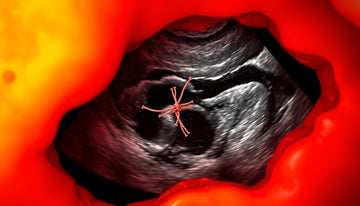

How Ultrasound Works in Identifying Retained Sutures

When ultrasound is utilized to investigate potential complications following surgical procedures, it can effectively visualize the presence of retained suture material. This imaging technique, ordered by a licensed medical professional, produces real-time images that allow for the examination of soft tissues and structures within the body. In the context of identifying retained sutures, ultrasound shows the location and appearance of these materials by highlighting their contrast against surrounding tissues. The terminology used in ultrasound reports often refers to the structural characteristics of the suture material observed on images, rather than indicating any symptoms or responses the patient may be experiencing. As with any ultrasound findings, a qualified healthcare provider will interpret these results in conjunction with a patient's history and physical examination to determine the appropriate course of action.